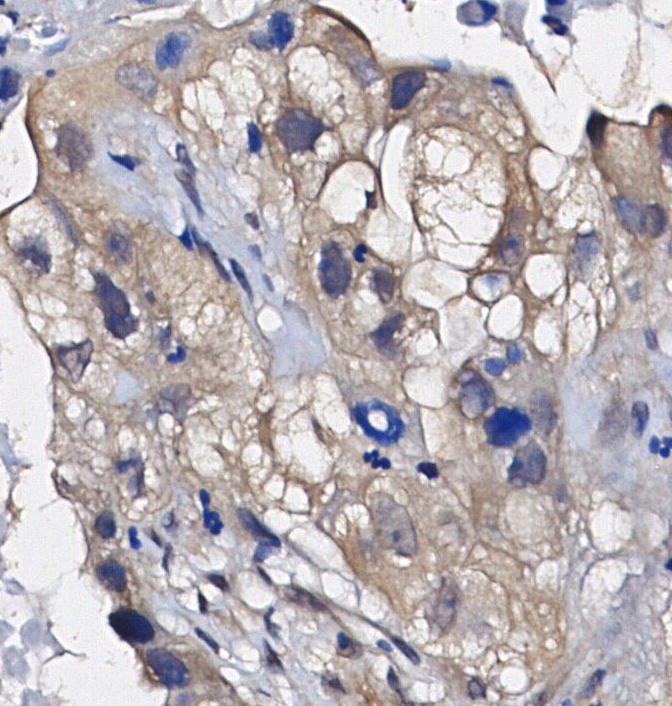

• Immunohistochemical analysis of formalin fixed paraffin embedded human Lung adenocarcinoma tissue with F0541 at 1/100 dilution.